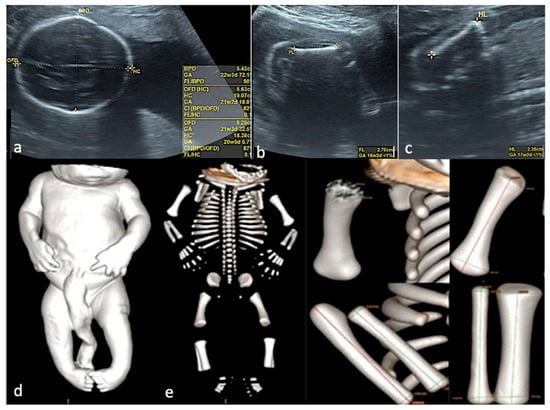

From Diagnosis to Decision—Fetal Limb Abnormalities

by Andreea Florentina Stancioi-Cismaru, Razvan Grigoras Capitanescu, Mihaela-Simona Naidin, Cristian Constantin, Marina Dinu, Florin Burada, Oana Sorina Tica, Mihaela Gheonea, Bianca Catalina Andreiana, Razvan Cosmin Pana and Stefania Tudorache

J. Clin. Med. 2026, 15(2), 486; https://doi.org/10.3390/jcm15020486 - 8 Jan 2026

Background/Objectives: Our aim was to investigate the diagnostic accuracy of prenatal ultrasound (US) in fetal limb abnormalities. As a secondary target, we wanted to correlate various predictors for the diagnosis accuracy. Methods: We prospectively enrolled cases with routine prenatal US performed in five [...] Read more.

Background/Objectives: Our aim was to investigate the diagnostic accuracy of prenatal ultrasound (US) in fetal limb abnormalities. As a secondary target, we wanted to correlate various predictors for the diagnosis accuracy. Methods: We prospectively enrolled cases with routine prenatal US performed in five participating centers. Subsequently, we selected and processed all cases with limb abnormalities: suspected, diagnosed, and missed on the prenatal diagnosis scans. We collected data on the type of anomaly, the US equipment and probes used, the operator’s expertise, the gestational age at the diagnosis, the length of the examination, and the use of US reporting form. SPSS 22.0 software was applied to perform the analyses using non-parametric statistical methods. Associations between categorical variables were evaluated using Fisher’s exact test and Chi-square tests. For correlations between the gestational age and the anomaly severity, we used Spearman’s rank-order correlation. Predictive performance of operator- and scan-related variables for diagnostic accuracy was assessed using receiver operating characteristic (ROC) curve analysis, with area under the curve (AUC) estimates, standard errors (SE), confidence intervals (95% CI), and p-values reported. Results: Our data showed that most US examinations were performed as part of routine screening (79.7%), and the most frequent anomaly diagnosed was clubfoot. Operators’ expertise demonstrated the highest predictive performance, while technical parameters—scan duration (AUC = 0.20, p = 0.1188) and US equipment (AUC = 0.30, p = 0.3478)—did not significantly predict diagnostic accuracy. Conclusions: The overall diagnostic accuracy of prenatal US was 85.5%. Our findings indicate that diagnostic performance is driven primarily by operator expertise and training, rather than by gestational age at scan and technical parameters. Full article

Show Figures

Figure 1